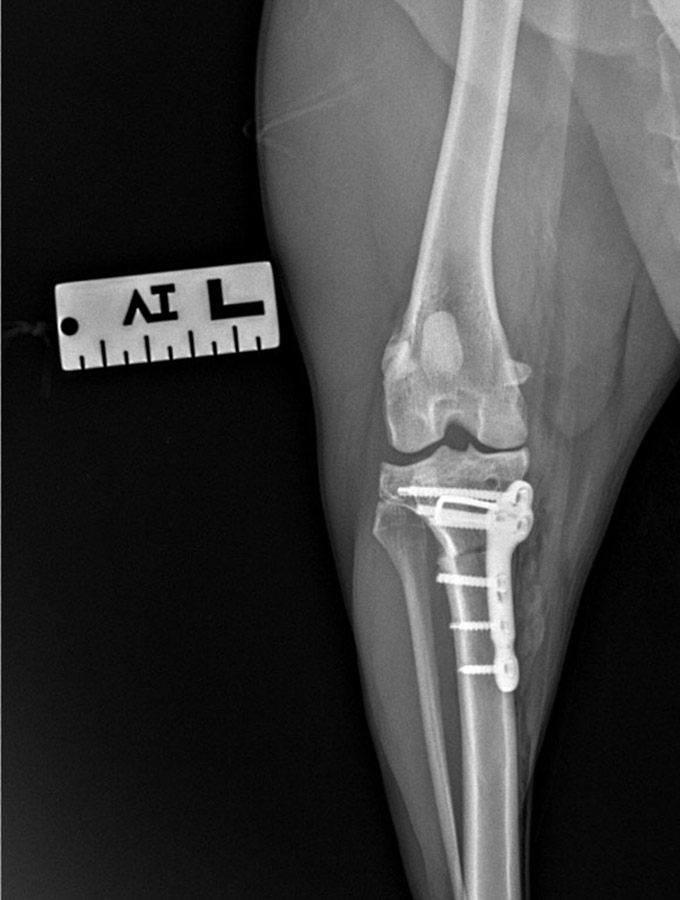

1. TPLO (Tibial Plateau Leveling Osteotomy), CCWO (Cranial Closing Wedge Osteotomy) i CBLO (CORA Based Leveling Osteotomy) – Zabiegi polegające na zmianie kąta powierzchni stawu piszczelowego przez wykonanie osteotomii.

2. TTA (Tibial Tuberosity Advancement), TTA Rapid oraz MTTA – Osteotomia, która polega na przesunięciu guzowatości kości piszczelowej, co zmienia biomechanikę sił działających na staw kolanowy.